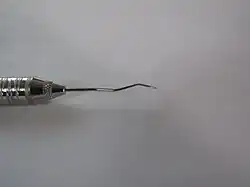

Dental explorer

Dental explorers, also known as sickle probes, are tools found in the dental arsenal that are frequently utilised. The explorer is designed with a sharp tip at the end to improve tactile perception.

There are various types of explorers, though the most common one is the No. 23 explorer, which is also known as a "shepherd's hook". Other types include the 3CH (also known as "cowhorn" or "pigtail") and No. 17 explorers, which are useful for the interproximal areas between teeth.

An 11/12 type explorer is a double-ended dental assessment instrument with mirror image working-ends.[4] The 11/12 dental explorer should be considered a dental hygienists most important instrument for the detection of subgingival and supragingival calculus. This instrument is used with the modified pen grasp and a feather light grip allowing for detection of both grainy and bindable deposits. Learning its adaptability is critical for the successful tactile sensations needed for the confirmation of calculus removal.

- The tip is at a 90- degree angle to the lower shank[4]

- The long intricate shank design makes it equally useful when working on anterior and posterior teeth with normal sulci or a deep periodontal pocket.[4]

- The design of the tip allows the back of the tip to be applied to the pocket base without lacerating the junctional epithelium, allowing adaptation to all surfaces throughout the mouth.[5]